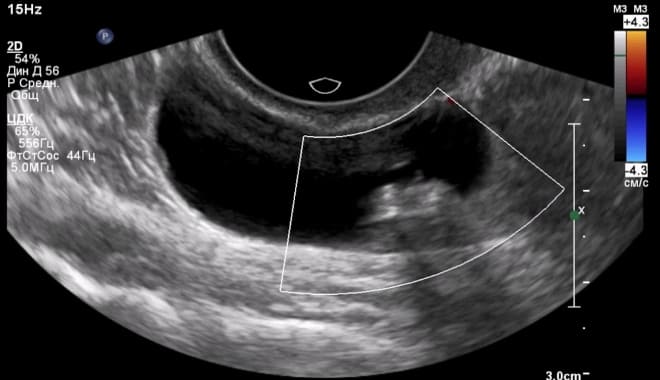

Как выглядит киста яичника на УЗИ

В гинекологии киста представляет собой полую опухоль, чаще всего доброкачественного характера, заполненную жидкостью.

Главным признаком кисты яичника при ультразвуковом исследовании является образование полого отростка на его поверхности. В отличие от нормального фолликула, который изменяется в течение менструального цикла, киста остается неизменной. Кроме того, такое образование обычно имеет больший размер.

На ультразвуковом снимке киста яичника отображается в виде черного пятна, размеры которого варьируются от 3 до 20 см.

Это округлая, гипоэхогенная структура с толстыми стенками. Полость кисты четкая и гладкая, без каких-либо включений.

Обычно размер кисты желтого тела составляет от 4 до 8 см. Благодаря наличию пристеночного кровотока, на ультразвуковом исследовании она выглядит как огненное кольцо.